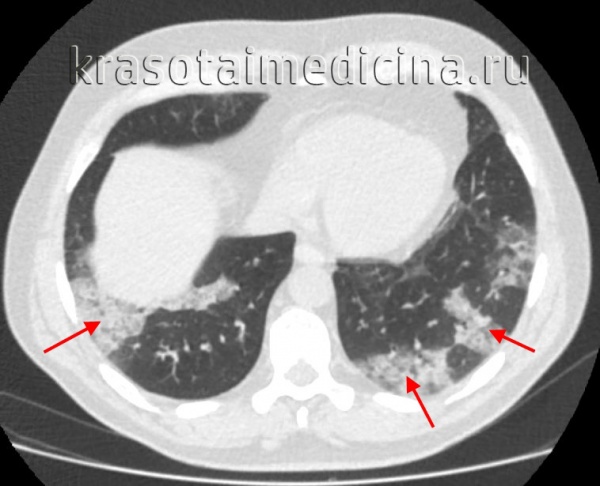

КТ ОГК. Множественные обширные участки снижения пневматизации по типу консолидации в нижних долях обоих легких.